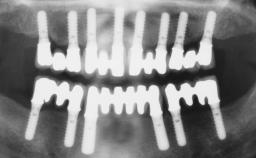

Immediate Loading of Six Implants in the Maxilla and Final Restoration with a Full-Arch Gold/Ceramic FDP Involving the Concept of Tilted Implants

A 61-year-old male patient with a failing fixed maxillary rehabilitation and a fixed mandibular rehabilitation requested a new fixed maxillary rehabilitation. The patient was wearing a temporary metal-reinforced maxillary bridge inserted two years before the consultation. He reported that his previous dentist did not want to insert a definitive framework because he considered the residual teeth to have a negative prognosis. The patient reported a history of recurrent caries and endodontic complications as the main reason for the previous extractions. The anamnesis was negative for periodontal disease and bruxism. The patient’s chief compliant was the mobility of his maxillary prosthesis, which needed to be re-cemented frequently, and discomfort during chewing.Moreover, the patient was not satisfied with the esthetic appearance of his maxillary teeth, which he found too long. The patient asked for a stable and comfortable fixed maxillary rehabilitation and firmly rejected any removable solution.

# of Implants 6

Type of Implants One-Piece|Reduced-Diameter

Defining Characteristics Fully edentulous upper jaw to be rehabilitated with four or more implants

Modality Fixed hybrid bridge on 5+ implants

Bone Volume Deficient horizontally, allowing simultaneous augumentation